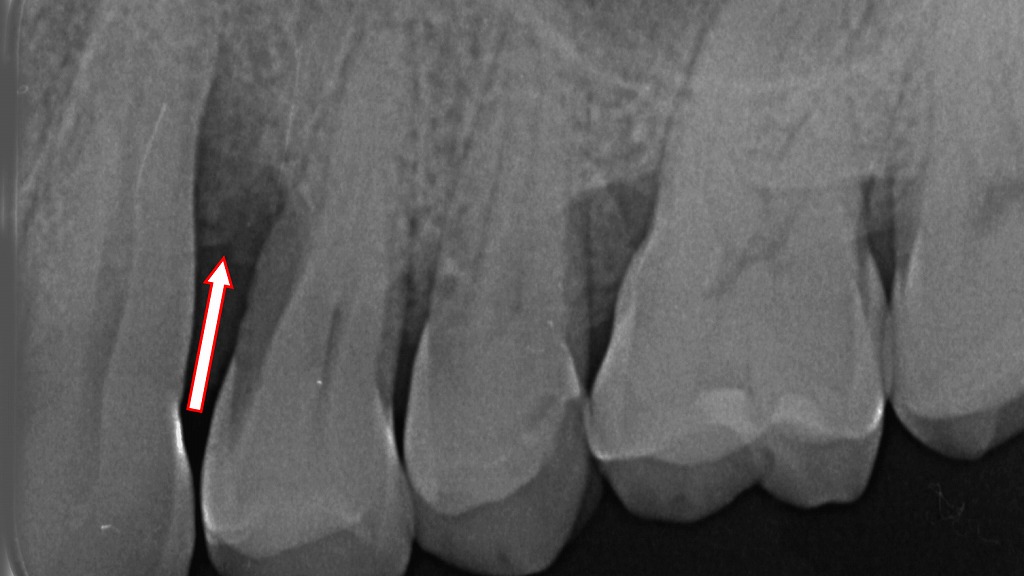

若年性歯周病(侵襲性歯周炎)による急速な骨吸収

赤矢印が示すように、下顎6番の歯根周囲に高度な骨吸収が認められます。若年性歯周病(侵襲性歯周炎)は10〜30代の比較的若い世代に発症しやすく、第一大臼歯・前歯(特に下顎6番・上顎6番・前歯)に骨吸収が集中する特徴があります。進行が非常に速いため、早期診断と徹底した歯周治療・メインテナンスが不可欠です。